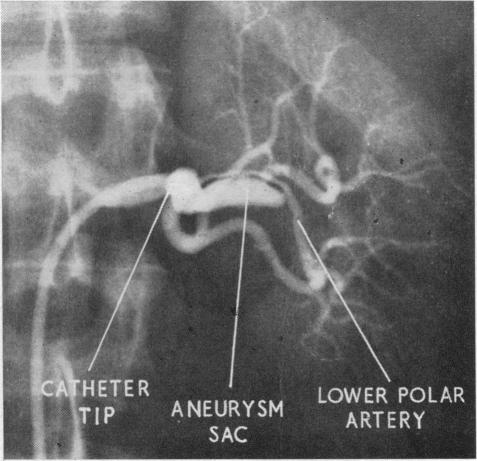

The diagnosis and treatment of renal-artery stenosis.

Br Med J. 1960 Jul 30;2(5195):327-38. doi: 10.1136/bmj.2.5195.327.